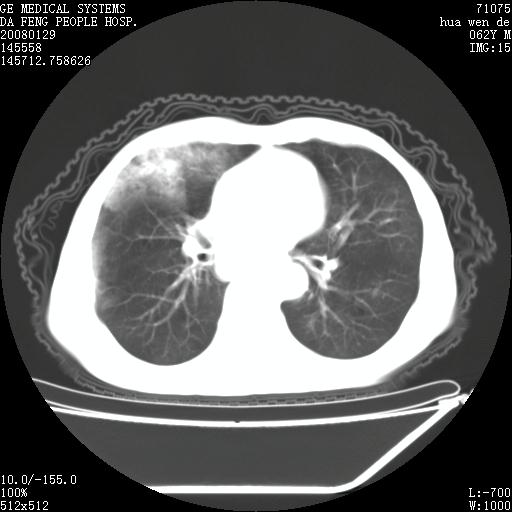

1.整个食管扩张,未见明显占位性病变,贲门区亦未见明显占位病变,考虑:贲门失驰缓症;

2.右上肺病变边缘可见毛刺,囊壁厚度不均匀,周围境界较清楚,未见炎性渗出性影,右上肺外带可见片状影,边缘不清,考虑:肺癌伴空洞形成、右上肺炎。

食管全程扩张,壁均匀不厚,喷门失弛缓症

右上肺空洞可见液平,临近肺野磨玻璃密度,考虑1.结核2.脓肿

右上肺空洞可见液平,临近肺野磨玻璃密度,考虑1.结核2.脓肿 支持!